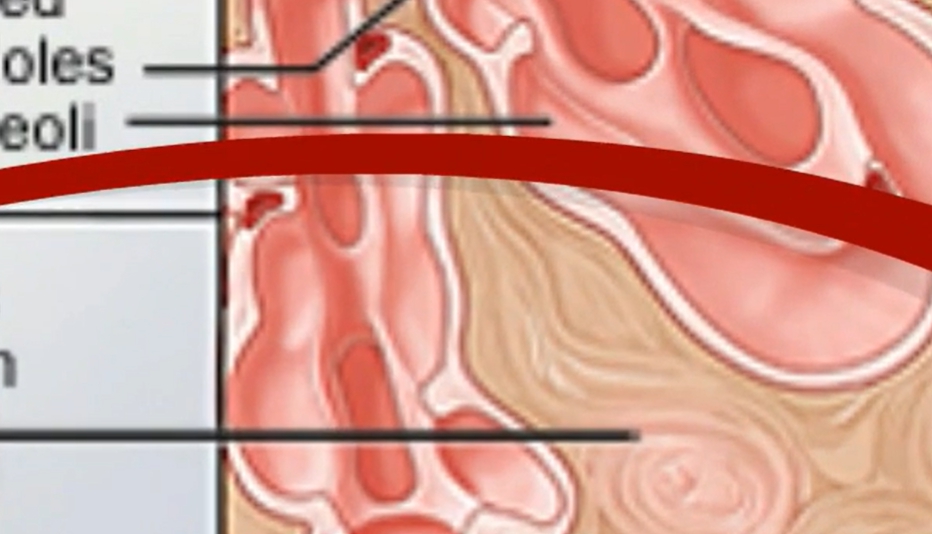

폐 섬유증은 폐에 염증이 반복되면서 정상적인 폐 조직이 점차 흉터 조직(섬유조직)으로 바뀌는 질환입니다. 이 섬유조직은 고무처럼 탄력이 없고 단단해, 한 번 형성되면 정상 폐로 되돌아가지 않는다는 특징이 있습니다. 이로 인해 폐가 충분히 팽창하지 못하고, 산소를 받아들이는 능력이 점점 떨어지게 됩니다.

- 산소가 혈액으로 제대로 전달되지 않음

- 깊게 숨을 들이마셔도 공기가 차는 느낌이 부족함

- 호흡을 할수록 숨이 가쁘고 피로가 쉽게 누적됨